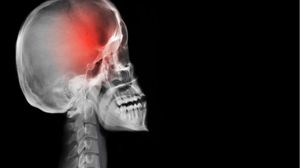

الوكيل الإخباري- قد تبدو أعراض مثل الصداع أو النسيان أو ضعف التركيز أمورًا عابرة، لكنها في بعض الحالات النادرة قد تشير إلى ورم في الدماغ، بحسب دراسة حديثة نشرها موقع Science Alert.

يحذّر الأطباء من أن تشابه أعراض الورم مع حالات شائعة مثل الإرهاق أو القلق قد يؤدي إلى تأخير التشخيص، مما يقلل فرص العلاج الفعّال.

أبرز الأعراض التي تستدعي الانتباه:

صعوبة في الكلام: مثل التلعثم أو عدم القدرة على تكوين جمل.

ضباب الدماغ: بطء في التفكير أو نسيان متكرر.

تنميل أو وخز: في جانب واحد من الوجه أو الجسم.

اضطرابات الرؤية: تشوش أو ازدواجية في النظر.

تغيّر في الخط أو تنسيق الحركة: خاصة في الكتابة.

تقلب المزاج أو السلوك: مثل العصبية أو اللامبالاة غير المبررة.

صداع غير معتاد: صداع يومي أو لا يستجيب للمسكنات.

إذا تكررت هذه الأعراض أو استمرت لفترة، يُنصح بمراجعة الطبيب لتقييم الحالة بدقة، خصوصًا إذا ظهرت أكثر من علامة في وقت واحد.